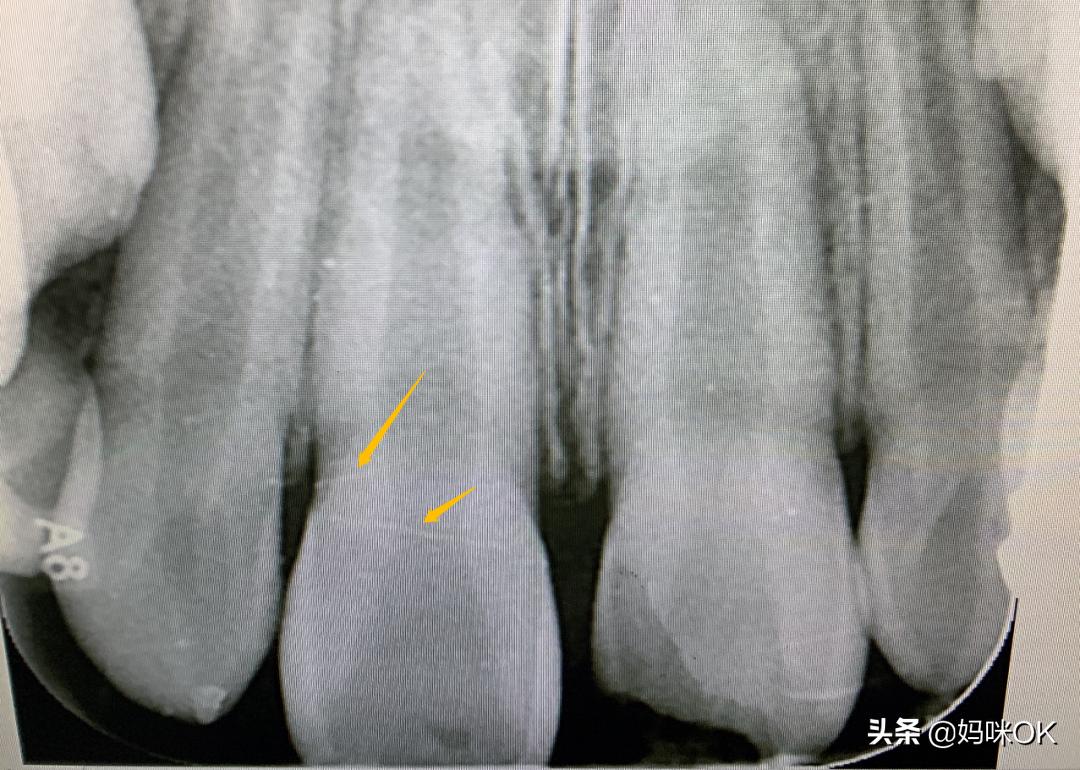

医生指着牙面上的裂纹和我说:“你看一下,虽说没伤到牙髓,但这次磕得也是说轻也不轻,两颗门牙都有不同程度的裂纹,尤其是没有磕破的那颗,反而裂纹更深。”

在光照下,我看到儿子的两颗门牙上赫然几条深深的裂纹↓ 除此还布满了细小的像陶瓷碗釉面的细格状裂纹(手机拍不下来)

这些裂纹在X光片上能清晰得看到,

说明相对比较深,也很容易在日后的使用中不断加深,导致牙齿的断裂。